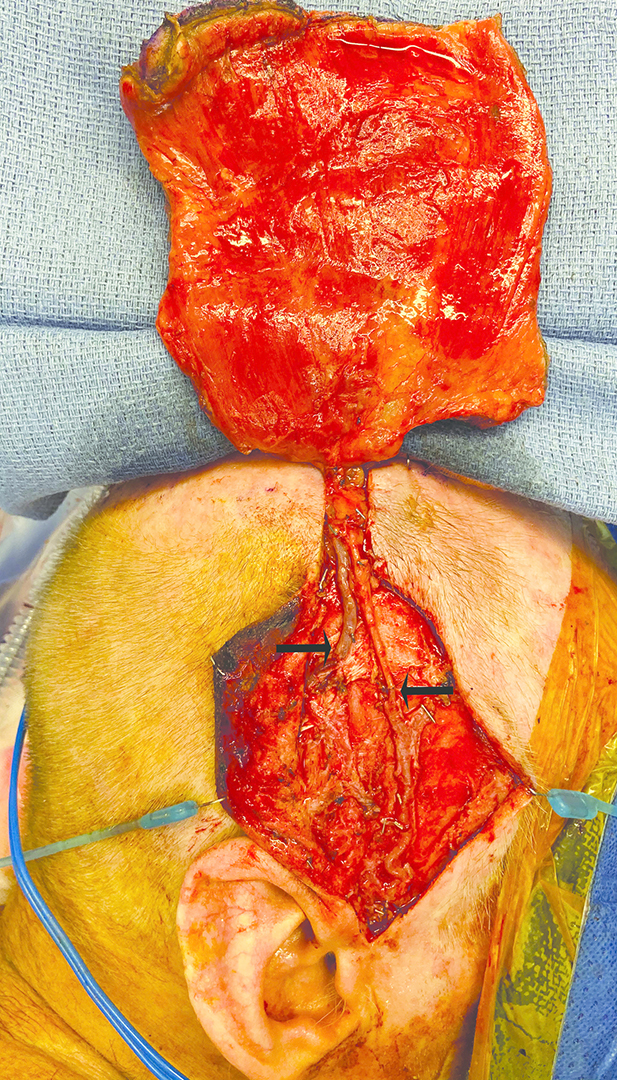

The latissimus dorsi (LD) free flap is our workhorse for scalp reconstruction. The patient is placed in a lateral decubitus position throughout the case. Therefore, the ipsilateral LD free flap is prerequisite if intraoperative re-positioning of the patient is to be avoided. Simultaneous preparation of the superficial temporal (ST) vessels as recipient vessels and LD free flap harvest are carried out by two separate teams. For defects over the scalp vertex, the recipient vessels are prepared 1–3 cm superior to the helical rim to decrease the length of free flap vascular pedicle necessary (Figure 1). Where the ST vein is not an appropriate recipient, a cephalic vein turn-up is preferred over a segmental inter-positional vein graft. The LD free flap is routinely harvested distal to the pedicle bifurcation, which requires intramuscular dissection of the vascular pedicle (Figure 2). This increases free flap pedicle length without the need to undertake tedious dissection in the axilla, as well as ensuring a better calibre match with the distal ST vessels. We have been able to regularly increase our pedicle length by 4 cm with this technique. This technique also allows us to exclude the bulkiest proximal triangular part of LD from the free flap for improved contouring. In patients where an LD free flap is used for coverage of the cranioplasty implant, a temporising skin paddle is required. In this situation, a thoracodorsal artery perforator (TDAP)–LD chimeric free flap is favoured. A segmental LD free flap is harvested if only a small flap is required.